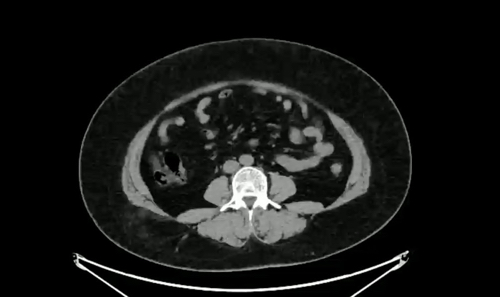

病例【腹盆】右侧臀部外伤,偶然发现,女,44岁。

【患者信息】:女,44岁。

【主诉】:右侧臀部外伤,偶然发现。